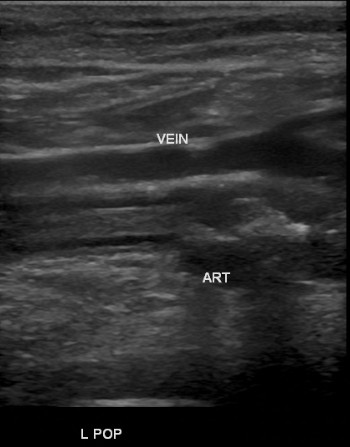

- After the pseudoaneurysm sac has thrombosed, the ultrasound technician must confirm and document patency of the adjacent artery and vein. Also, palpate the pulses, and document that they have not changed compared to before the procedure.